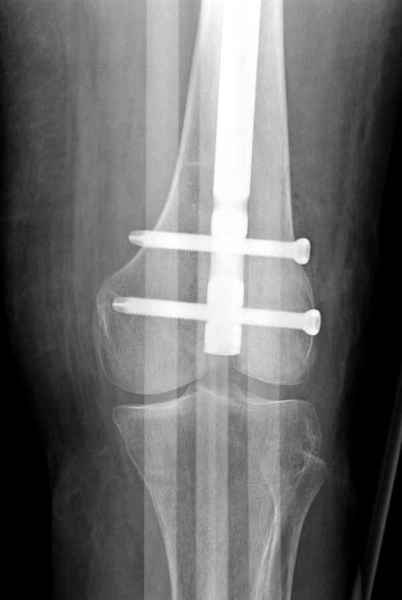

С минимальным рассверливанием и ретроградным методом провели остеосинтез бедра 12 мм гвоздем. (17-20)

Кровопотеря во время операции меньше 100 мл.

Больная выписана, взятый во время рассверливания материал изучается.